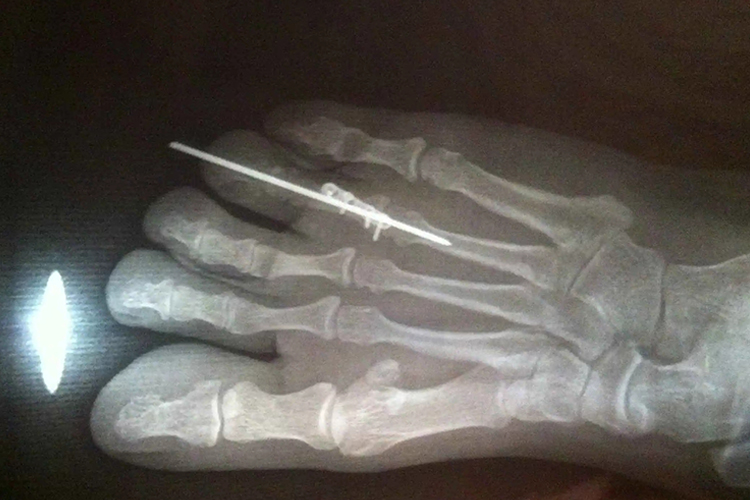

脚趾骨折多为重物压砸或踢碰硬物所致,脚趾骨折打钢钉是指用钢钉内固定脚趾趾骨的断端,防止骨折移位,有助于骨折的恢复。

脚趾骨折打钢钉时常需要钢钉内固定脚趾趾骨的断端,以防止移位,促进骨折面愈合,而且骨折后所使用的钢钉具有良好的生物相容性,人体不会对其起排斥反应。